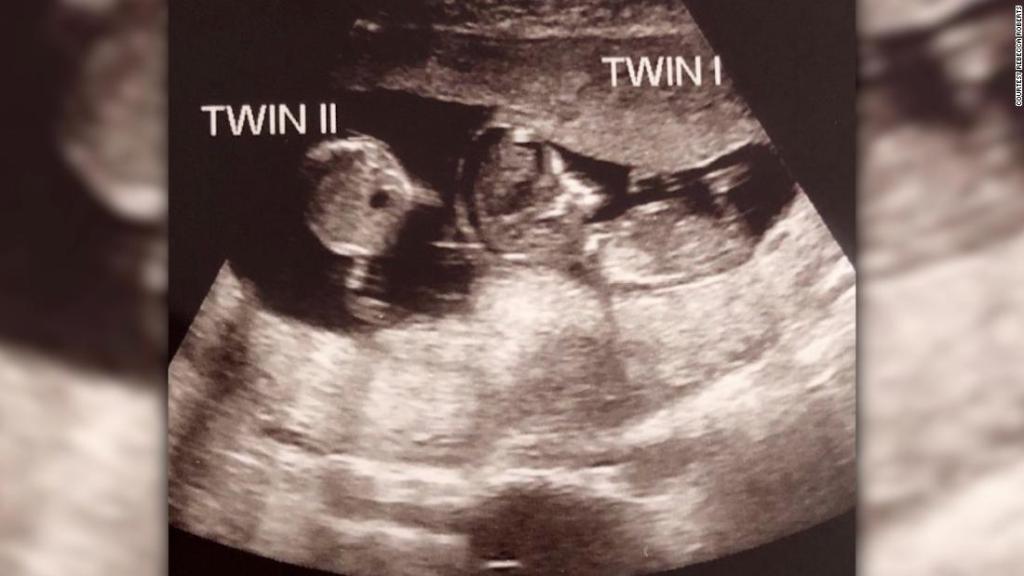

Una ecografía que fue tomada en la semana 12 mostró que Noah tenía una inesperada hermana pequeña, su gemela fraterna, Rosalie.

Los médicos le dijeron a la pareja que los bebés fueron concebidos con tres semanas de diferencia, dijo Rebecca.

“Se dieron cuenta de que el bebé estaba creciendo a un ritmo constante de tres semanas menos que el primero, y fue entonces cuando me dijeron que creían que era un embarazo de superfetación", indicó.